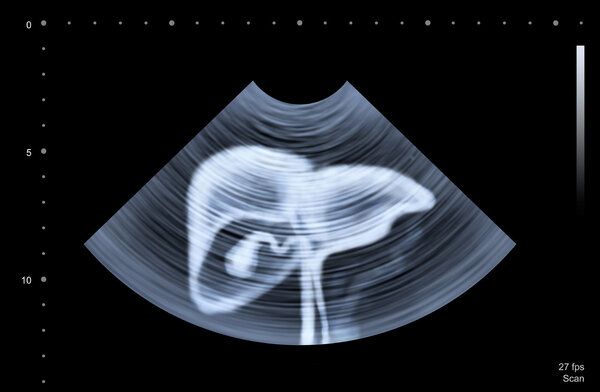

肝脏腹膜后肿瘤的严重性与肿瘤大小、生长速度、是否侵犯周围结构以及是否有远处转移等因素有关。对于良性肿瘤且无明显症状者,一般不严重,定期复查即可;而对于恶性肿瘤,则比较严重,因为恶性肿瘤具有侵袭性和转移性,可导致器官功能受损,甚至引起全身衰竭。因此,针对不同类型的腹膜后肿瘤,应采取不同的处理措施,建议患者及时就医,以便获得专业的诊疗意见。

如果肿瘤为恶性的,且已经发生扩散或转移至其他部位,则属于较为严重的情况,可能危及生命健康。

针对肝脏腹膜后肿瘤的诊断和治疗需谨慎对待,避免不必要的手术风险,并确保在专业医生指导下进行。